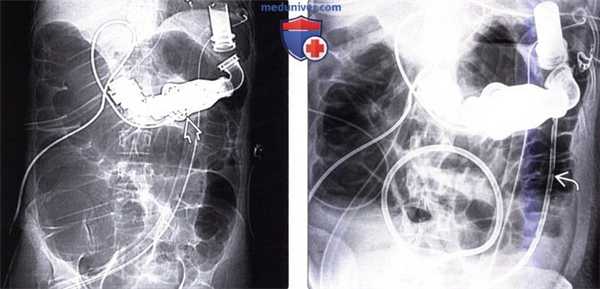

(Слева) На рентгенограмме у женщины 42 лет с кардиомиопатией, которой был внедрен аппарат для поддержки функции левого желудочка , на фоне чего появилась боль и вздутие живота, определяется выраженная дилатация толстой кишки. Диаметр слепой кишки составляет 11 см, поперечной ободочной — 8 см. На КТ, тем не менее, измеренный диаметр слепой кишки составляет 8 см, а поперечной ободочной -6 см.

(Справа) На рентгенограмме у этой же пациентки визуализируется дренажная трубка , установленная в просвете кишки во время эндоскопической процедуры, в результате чего была осуществлена декомпрессия, приведшая к уменьшению выраженности симптоматики.